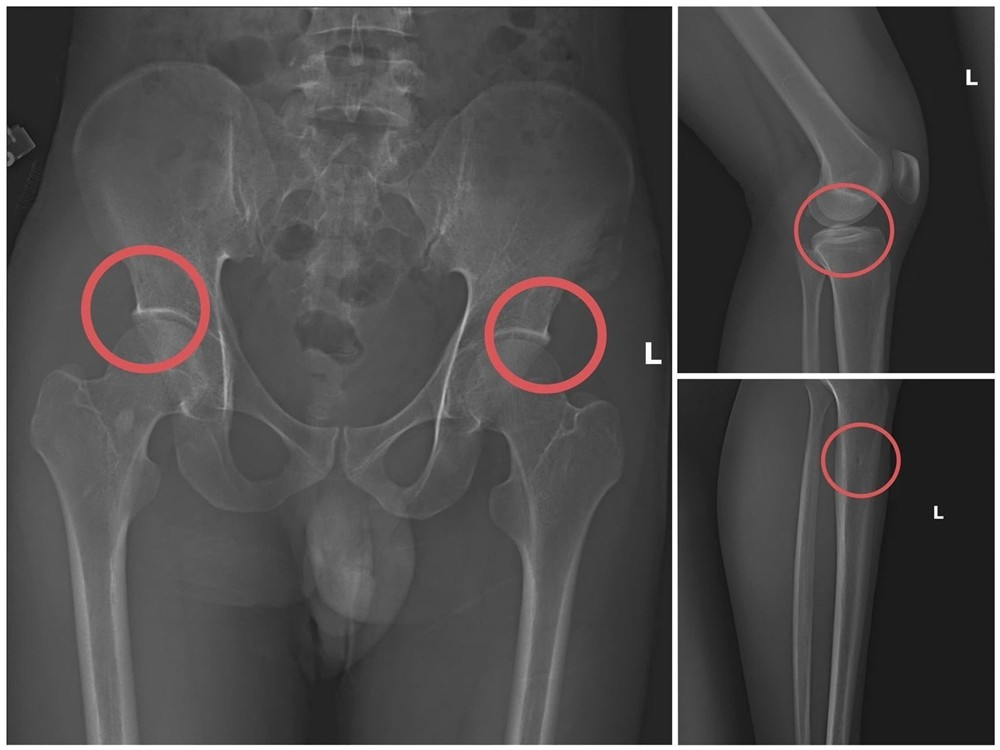

Châu trực tiếp thực hiện hành vi tiêm thuốc mê, sau đó sử dụng kim tiêm, búa, đinh để tác động vào xương người mua bảo hiểm, tạo nên những vết nứt, vỡ xương như tai nạn thật. Khi thương tích đã được tạo ra, Châu hướng dẫn các đối tượng dựng hiện trường giả như điện giật, trượt chân ngã suối… nhằm hợp thức hóa bệnh án và hoàn thiện hồ sơ yêu cầu chi trả. Thủ đoạn này được đánh giá là tàn nhẫn, vô nhân tính, coi thường đến sức khỏe và tính mạng người tham gia, đồng thời được tính toán kỹ lưỡng để gây thương tích tại vị trí có mức chi trả cao, khiến các công ty bảo hiểm khó phát hiện dấu hiệu gian dối.